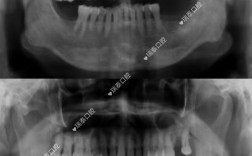

种牙作为修复缺失牙的有效方式,其成功与否与术前检查密切相关,全面的术前检查能评估患者是否适合种牙,确定最佳种植方案,降低手术风险,提高种植体的长期成功率,种牙前的检查涉及口腔局部、全身健康状况、影像学等多个维度,需要系统、细致地完成,口腔局...